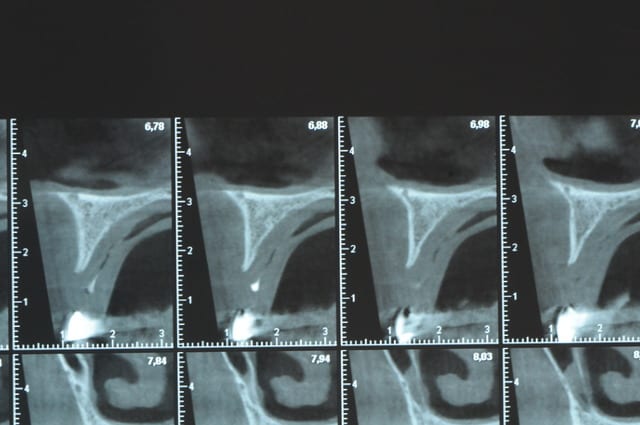

Une petite étude de ton cas D57

Les zones exploitables radiologiquement parlant:

Coupes implant

2,3 40100

4,96 35130 avec sinus lift mais difficile

5,25 35150

6,02 35130

6,78 35115 après réduction de hauteur de crête

7,26 35115 après réduction de hauteur de crête

8,51 35150

10,43 40115 ou 50115

11,10 40115

Ce qui nous fait 9 implants possible évidement avec un comblement de sinus on augmenterait encore les zones implantable mais ce n’est pas le but recherché, avec 8 (4+4) il doit être possible de faire une belle barre support de complet